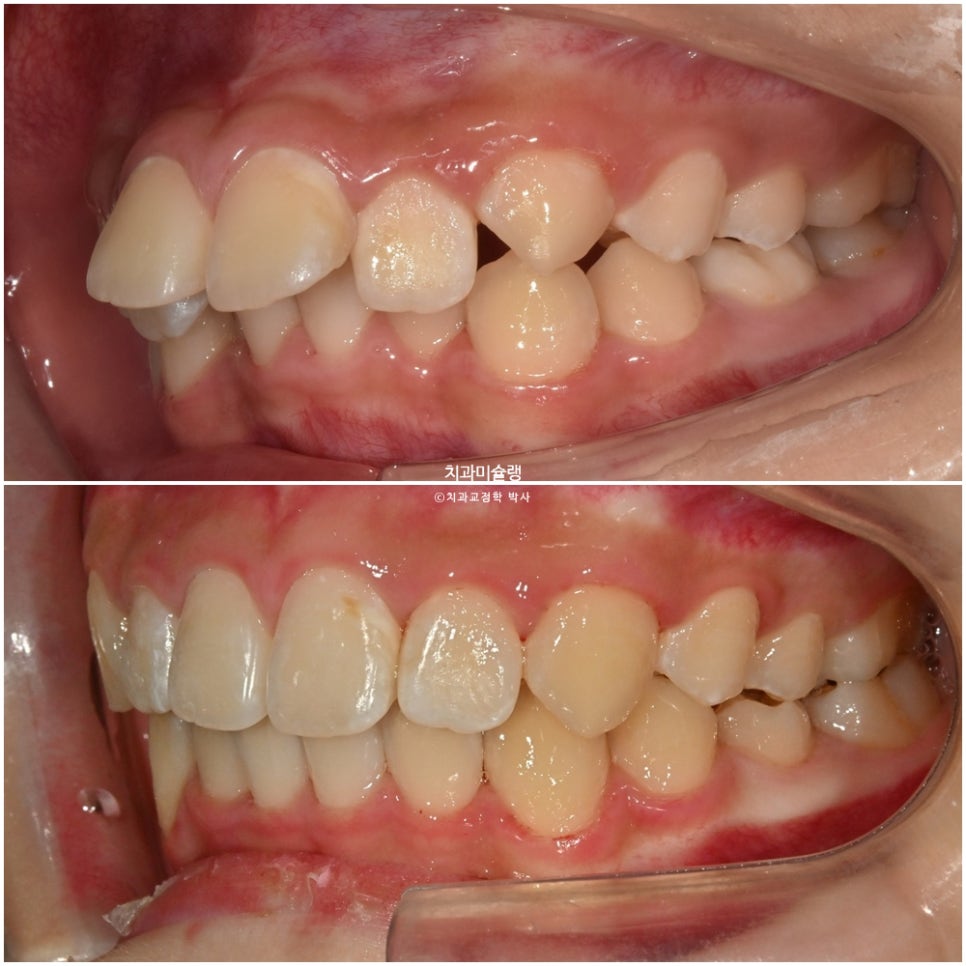

좌우 교합관계가 모두 2급이며 특히 좌측이 더 심합니다.

어금니 교합관계는 고무줄을 계속 걸었던 우측은 1급을 달성, 고무줄을 못걸었던 좌측은 여전히 2급 입니다.

배열은 좋습니다. 일년사이 마지막 남아있던 유치가 빠지고 영구치가 올라왔습니다.

어금니 교합관계는 양쪽다 1급을 달성.

2급 교합관계가 1급 교합관계로 개선되었습니다.

송곳니가 유난히 뾰족하긴 하지만, 시간이 지나면 자연스럽게 마모되므로 어린 나이를 고려하여 따로 치아성형은 하지 않습니다.